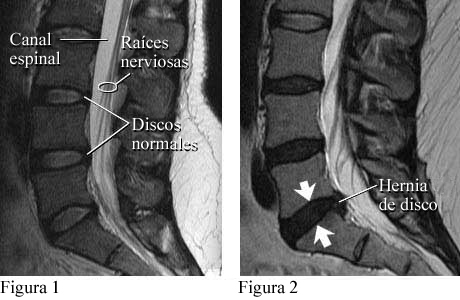

Examen de imágenes por resonancia magnética de la columna lumbar